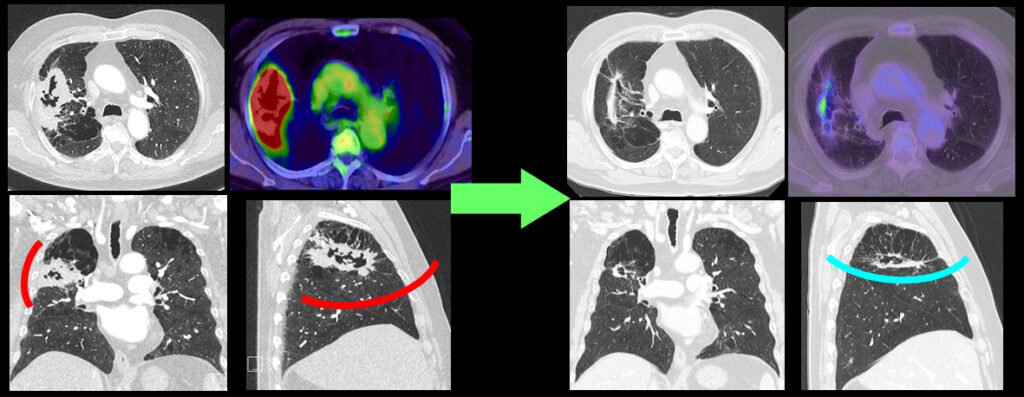

【症例3】下図左)右上葉から中葉にかけて大きな病変が存在し胸壁にも接している。cT4N0M0 IIIA期相当で、この時点でも手術による摘出は可能であるが、はじめから手術を行うと開胸による右上中葉切除、あるいは、右上葉切除と中葉の半分程度を合併切除する必要がある(赤ライン)。化学免疫療法後、右)腫瘍がよく消退し、胸腔鏡で右上葉切除の残った病変を摘出(水色ライン)し得て、低侵襲に完全切除し得た。(同様の病態で同様の結果を保証するものではありません。)

【症例4】下図左)左上葉の主病変は肺門~縦隔に転移しcT2bN1~2M0 IIB~IIIA期相当である。化学免疫療法実施後、右)腫瘍は少し小さくなっているが、転移リンパ節はそのまま残っている。この症例は上記3例に比べると反応が乏しく、気管支形成と血管形成を併用した複雑な左上葉切除を行った。完全切除が得られ、術後の補助化学療法を実施している。(同様の病態で同様の結果を保証するものではありません。)